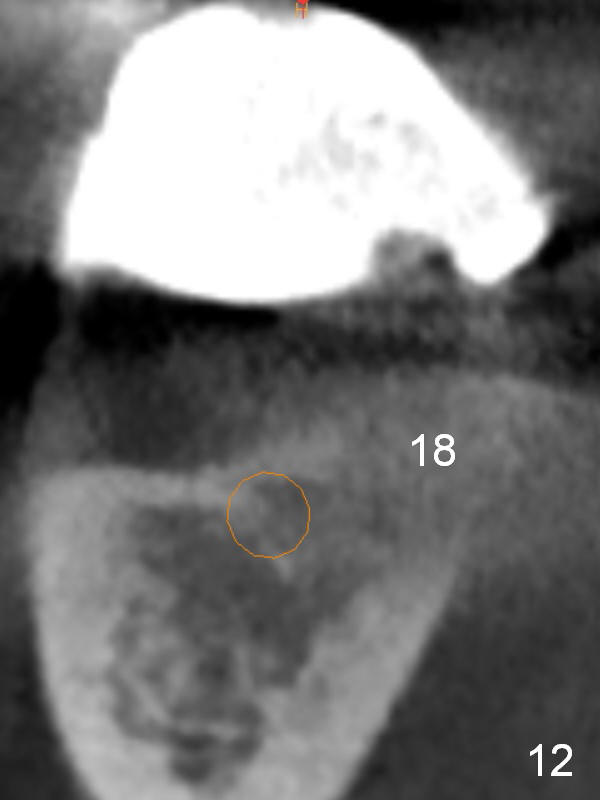

The patient wants to change unstable complete dentures to fixed ones.  Because the problem of pain is associated with the lower left (Fig.1 the left Inferior Alveolar Nerve is more superficial), the lower arch will be reconstructed first.  Totally 6 implants will be placed for bridges/crowns.  Due to time constraint, four implants are placed at the 1st stage (#21, 22, 27 and 28 (Fig.4,5,8,9)); the lower denture will be retained immediately by ball abutments and soft relined.  Two to three months later, two more implants will be placed (at #31 and 20, Fig.2,10).  Note severe atrophy of the crest at #18 and 19 (Fig.11 and 12).  If primary stability is achieved, a fixed immediate provisional will be fabricated.

In contrast to the upper arch, the bone density in the lower arch is high.  The challenge is bone height.  Short implants will be used (6 mm for #31 (Fig.2) and 8 mm for the majority of the others (at premolar and canine sites).  If needed, extra implants will be placed at incisor sites (Fig.6,7 (implant can be longer)) and at #29 (Fig.3) .  If a site is too small for a 3.8 mm 2-piece implant, a 1-piece one may be placed.